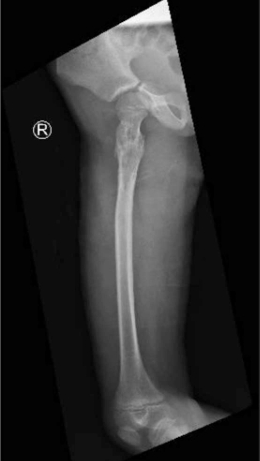

随访观察:随访期间发现,因患儿生长发育导致克氏针逐渐向股骨颈远端移位,使愈合周期延长——这恰是选用光滑克氏针而非螺钉的优势所在。图6展示了术后1年的影像资料。术后两年半,骨愈合完全,患者返院取出内固定物(图7)。内固定去除后1年随访显示(图8),股骨颈重塑至正常颈干角,末次随访时患者关节无僵硬、活动度无受限、无疼痛及跛行。